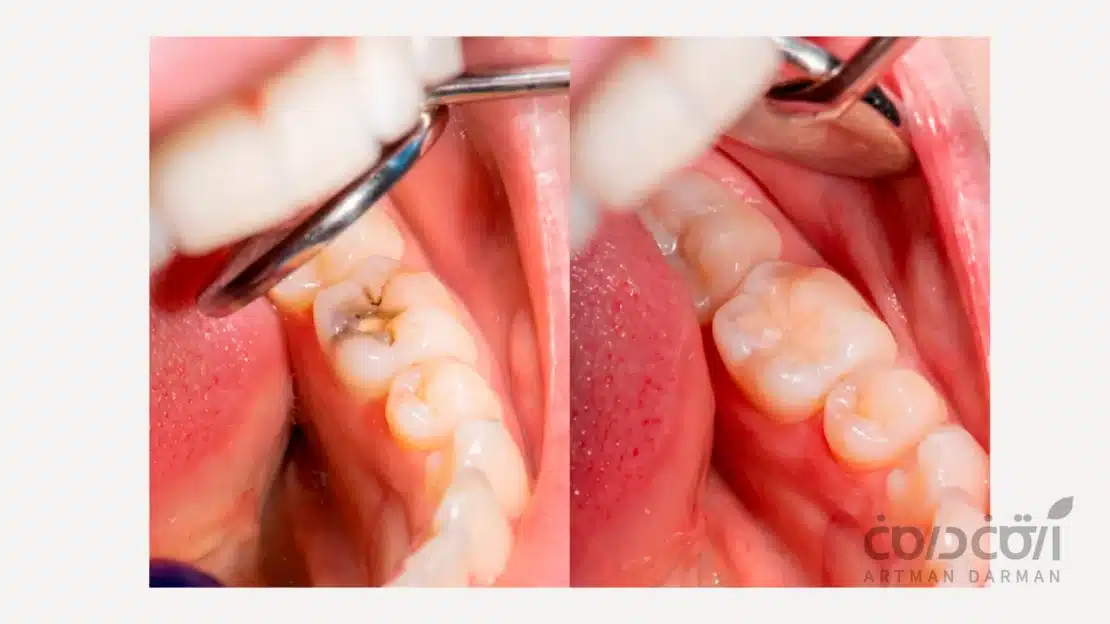

متاسفانه از سالیان دور یک باور اشتباه وجود دارد که بعد از درمان ریشه (عصب کشی) حتما باید دندان را روکش کرد! این باور چندان درست نیست چراکه برای نصب روکش (به عنوان پروتز) نیاز است دور تا دور دندانِ درمانِ ریشه شده را تراشید (با وجودی که ممکن است سالم هم باشد). بنابراین این درمان تهاجمی است و به همین دلیل در دندانپزشکی مدرن ترجیح این است که روکش به عنوان آخرین روش ترمیم در نظر گرفتهشود. درمان جایگزین در این روزها بیلداپ دندان است. در این روش دندان درمان ریشه شده از نو با کامپوزیتهای زیست سازگار بازسازی شده و نه تنها عملکردش حفظ میشود، بلکه از نظر ظاهری نیز کاملا طبیعی و مشابه با دندان های دیگر خواهد بود.